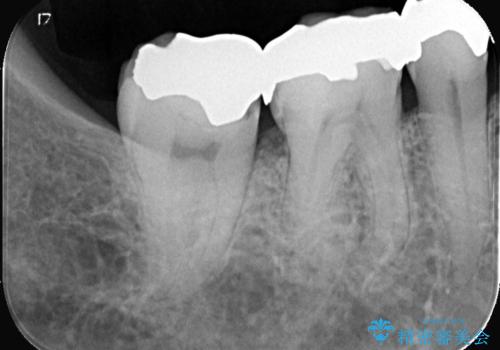

- 当院にメインテナンスで通っていただいている患者様です。銀歯の下の虫歯が大きくなってきたので、治療を行いました。

銀歯を外し虫歯を除去後、オールセラミッククラウンで治療を行いました。

銀歯は錆びる金属が使用されており、型取りの材料も変形がある材料になってしまうので、再び虫歯になってしまっている患者さんが沢山おられます。